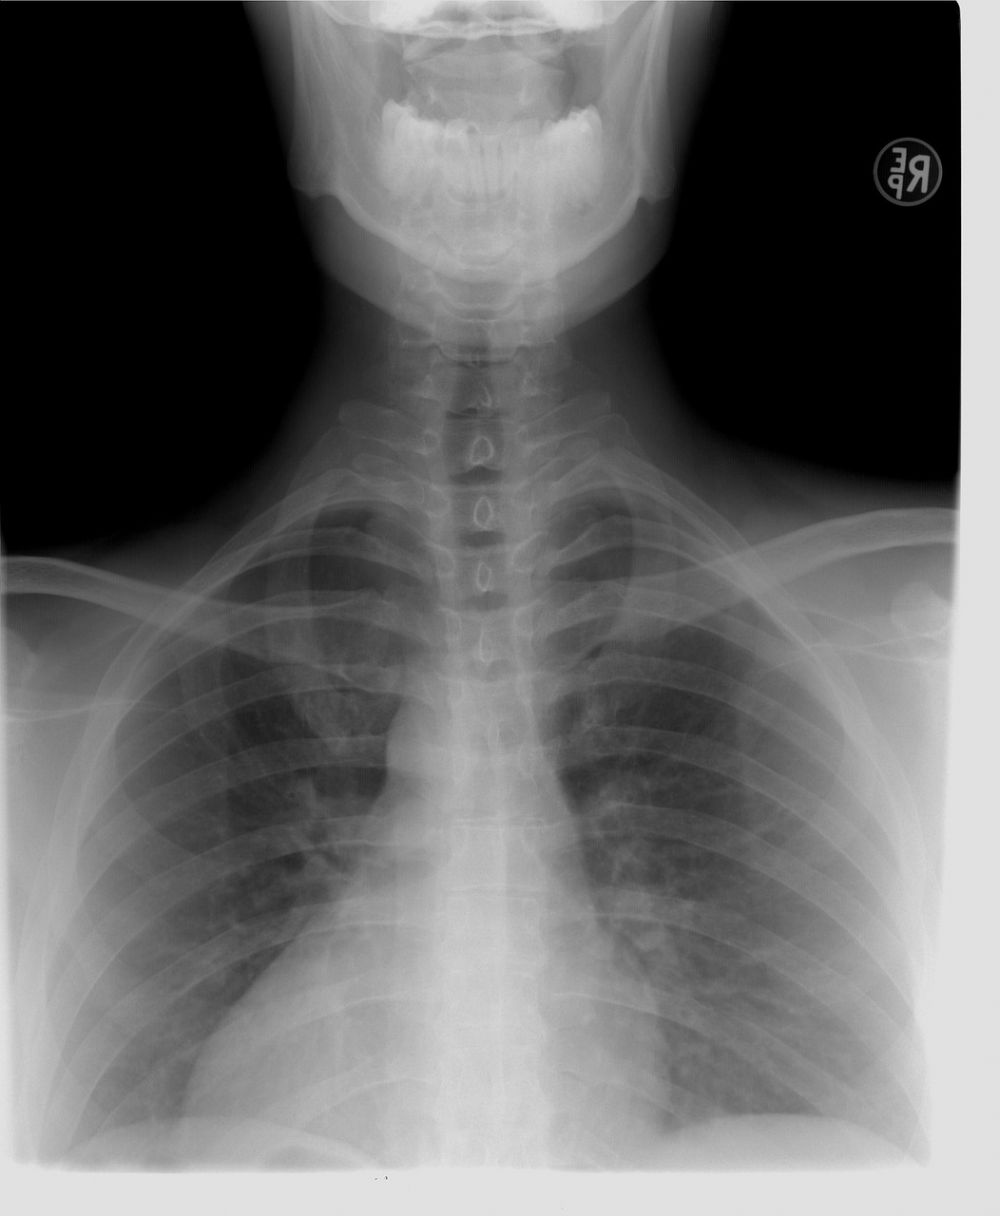

Røntgenundersøgelse sådan foregår den, og det skal du vide

En røntgenundersøgelse er en af de mest brugte metoder i sundhedsvæsenet til at undersøge knogler, lunger og en række andre strukturer i kroppen. Undersøgelsen bruges til at stille diagnose, vurdere skader og følge udviklingen i en sygdom. Mange forb...